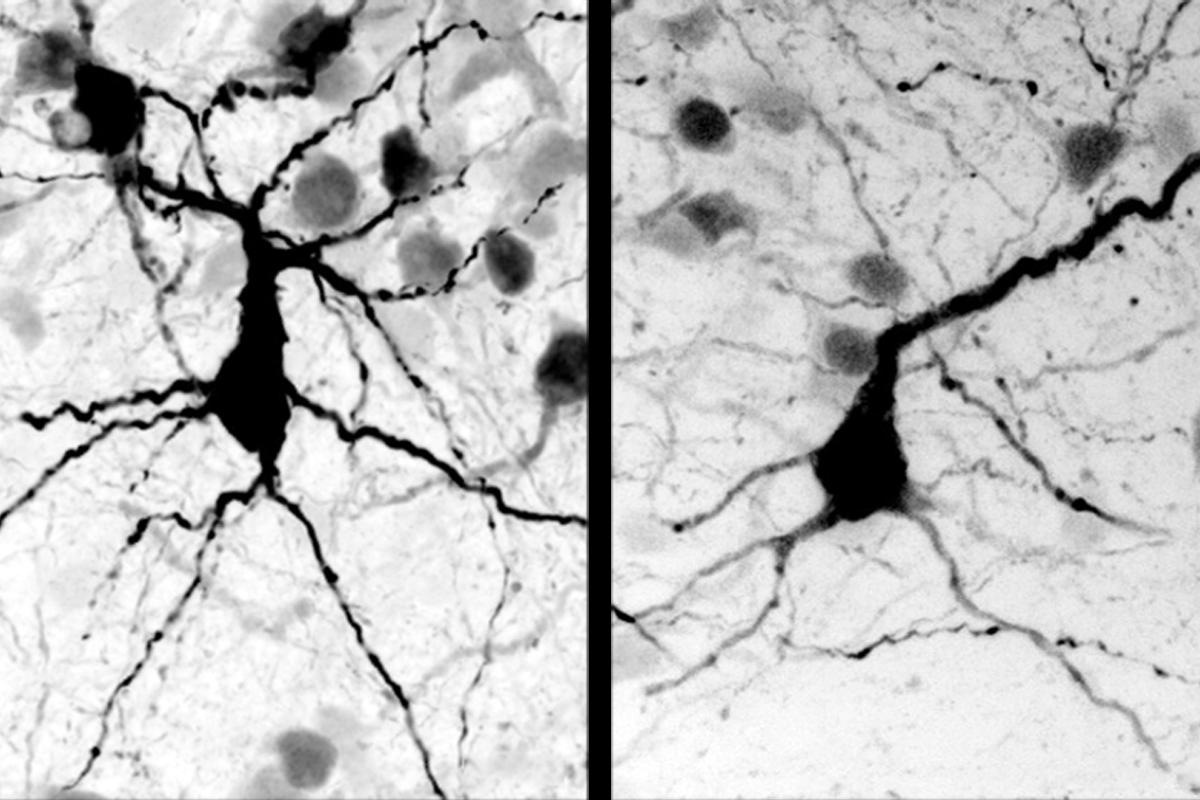

Altered growth: Neurons in cerebral organoids containing a MECP2 variant (right panel) have smaller cell bodies and fewer branches than those in wildtype organoids (left panel). - “SYNGAP1 and the development of murine neocortical progenitor cells” Nature Communications